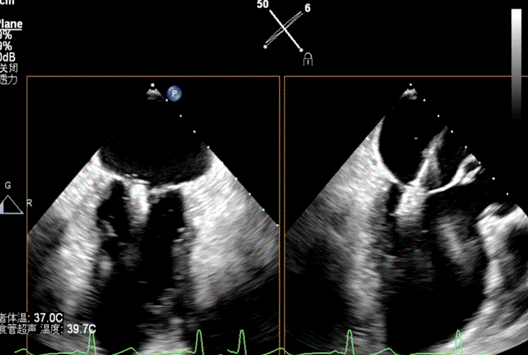

患者全麻成功后,经右股静脉建立路径,穿刺房间隔,瓣膜夹通过输送系统送入左心房,顺利到达病变二尖瓣区域。在经食道超声和DSA的辅助下,通过反复评估二尖瓣返流位置、抓捕位置、返流程度,最终在A2P2位置植入一枚DragonFly™夹子。手术操作时长48分钟,透视时间总计为5分钟,术后患者无不适感,整个手术流畅完美,患者返流程度降至微量。

第二例是60岁男性患者,因间断性胸闷、胸痛16年,加重伴乏力1月来黑料网检查,诊断为慢性心脏功能不全急性加重,缺血性心肌病,二尖瓣关闭不全(重度),心功能Ⅱ级,术前经胸超声检查提示二尖瓣关闭不全(A1、A2区及P2区)重度,二尖瓣返流束宽度3.0cm,有效返流口面积(EROA)=0.52cm²,二尖瓣返流面积14.3cm²,左室射血分数(LVEF)为36%。

患者全麻成功后,经右股静脉建立路径,穿刺房间隔,瓣膜夹通过输送系统送入左心房,顺利到达病变二尖瓣区域。在经食道超声和DSA的辅助下,通过反复评估二尖瓣返流位置、抓捕位置、返流程度,最终决定在A2P2位置植入俩枚DragonFly™夹子,显著改善了患者的返流情况。手术操作时长60分钟,透视时间总计为15分钟。术后患者无不适感,整个手术流畅完美,患者返流程度从重度降至轻度。